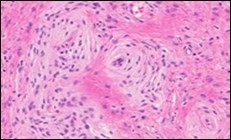

Figure 4.Soft tissue perineurioma composed of whorls and perivascular aggregates of neural cells with bipolar cytoplasmic processes, wavy, slender nuclei and commingled collagen fibres 13.